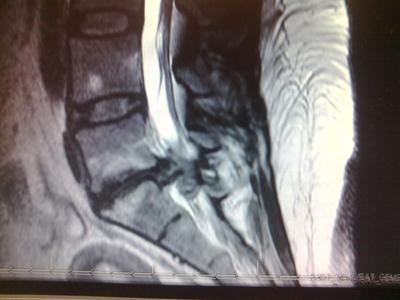

Doc sent me for a second MRI. I mentioned the MRI tech, I hoped they could see what was wrong, and he replied: don't worry...let's just say if a picture is worth 1,000 words, yours is worth 10,000. I've attached an image of that MRI. Apparently I had had herniated the disk, with the disk material squishing out and pressing on my sciatic nerve! And more spinal stenosis. Ah ha! That explained it! I was off work a couple months waiting for a cortisone shot, which worked great!!!! Completely FINE for about 3 months.

That scan isn't indeed great; can you see also that whiteness in the bone? It's called a modic effect meaning that fluid has seeped into the bone. Pain.